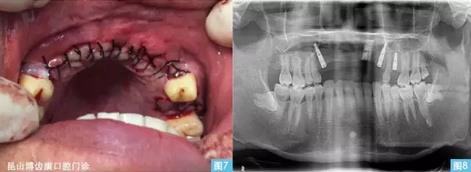

圖7圖8:(左圖7)黏膜對位縫合,(右圖8)種植術(shù)后曲面體層攝影。